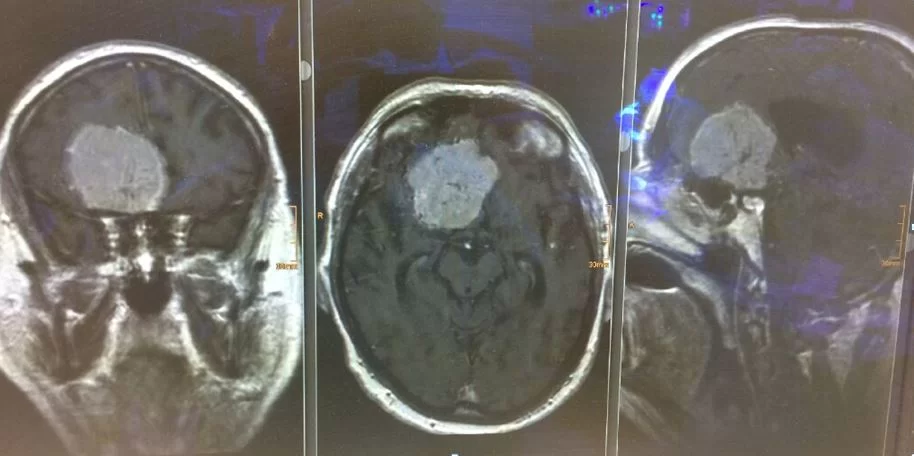

Αισθησιονευροβλάστωμα (οσφρητικό νευροβλάστωμα)

Ασθενής άνδρας, 44 ετών με διαταραχές προσωπικότητας, κεφαλαλγίες και ανοσμία. Επείγουσα εισαγωγή λόγω απώλειας όρασης και βυθιότητας. Η αξονική και μαγνητική τομογραφία εγκεφάλου ανέδειξε γιγαντιαία